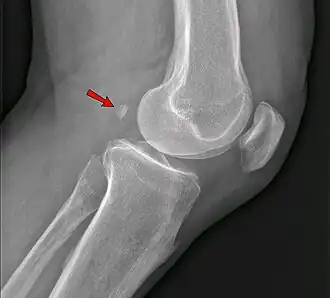

Genou